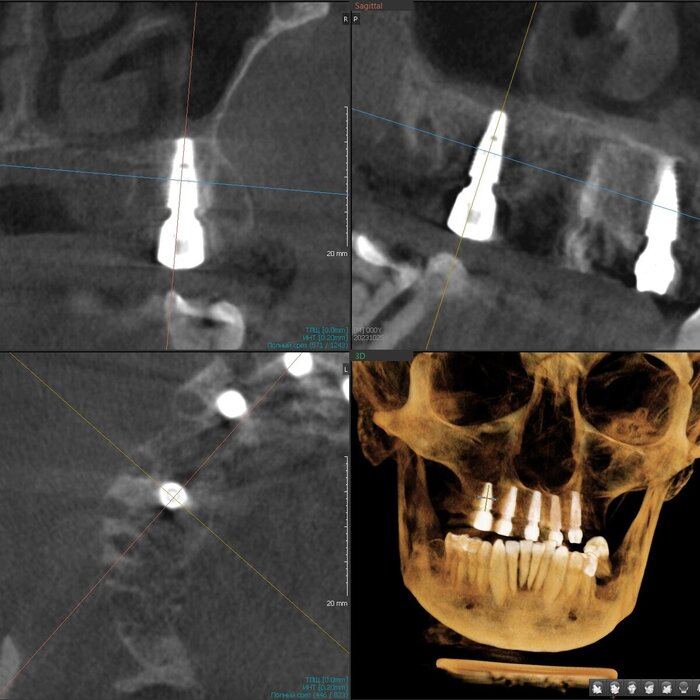

Имплантаты установлены - 5 штук. Были мысли насчёт 6-ти, даже шаблоны сделаны с этим расчётом. Но - обильное кровотечение и малек количество кости не оставили шансов. Мы не рискуем. Делаем на 5-ти, 6-ой имплантат будет установлен позже, через несколько месяцев.

Делаем промежуточное фото. Это нужно, что бы хирург видел, есть ли необходимость имплантаты "докрутить". Да, есть - 2 штуки можно углубить на 2 мм каждый.

Ещё раз контроль - финишный.

Давайте посмотрим на каждый имплантат - на все 5 штук.

1. Область зуба 2.4.

2. Область зуба 2.2

3. Область зуба 1.2

4. Область зуба 1.4

5. Область зуба 1.7

Всё хорошо. Всё отлично. У Егора Романовича настоящий талант, опыт, знания и, к тому же, искренняя любовь к своему делу.

Операция была проведена без откидывания лоскутов - пациент избавлен от послеоперационных болей и отёков.